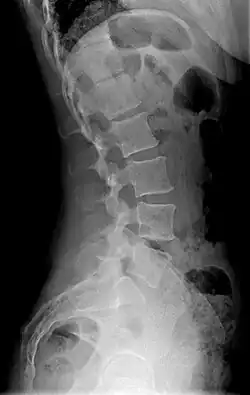

Diagram showing normal curvature (posterior concavity) of the cervical (neck) and lumbar (lower back) vertebral column (spine) | |

Precise diagnosis is done by looking at a complete medical history, physical examination, and other tests of the patient. X-rays are used to measure the lumbar curvature. On a lateral X-ray, a normal range of the lordotic curvature of between 20° and 60° has been proposed by Stagnara et al., as measured from the inferior endplate of T12 to the inferior endplate of L5.[18] The Scoliosis Research Society has proposed a range of 40° and 60° as measured between the upper endplate of Th12 and the upper endplate of S1.[18] Individual studies, although using other reference points, have found normal ranges up to approximately 85°.[18] It is generally more pronounced in females.[18] It is relatively constant through adolescence and young adulthood, but decreases in the elderly.[18]